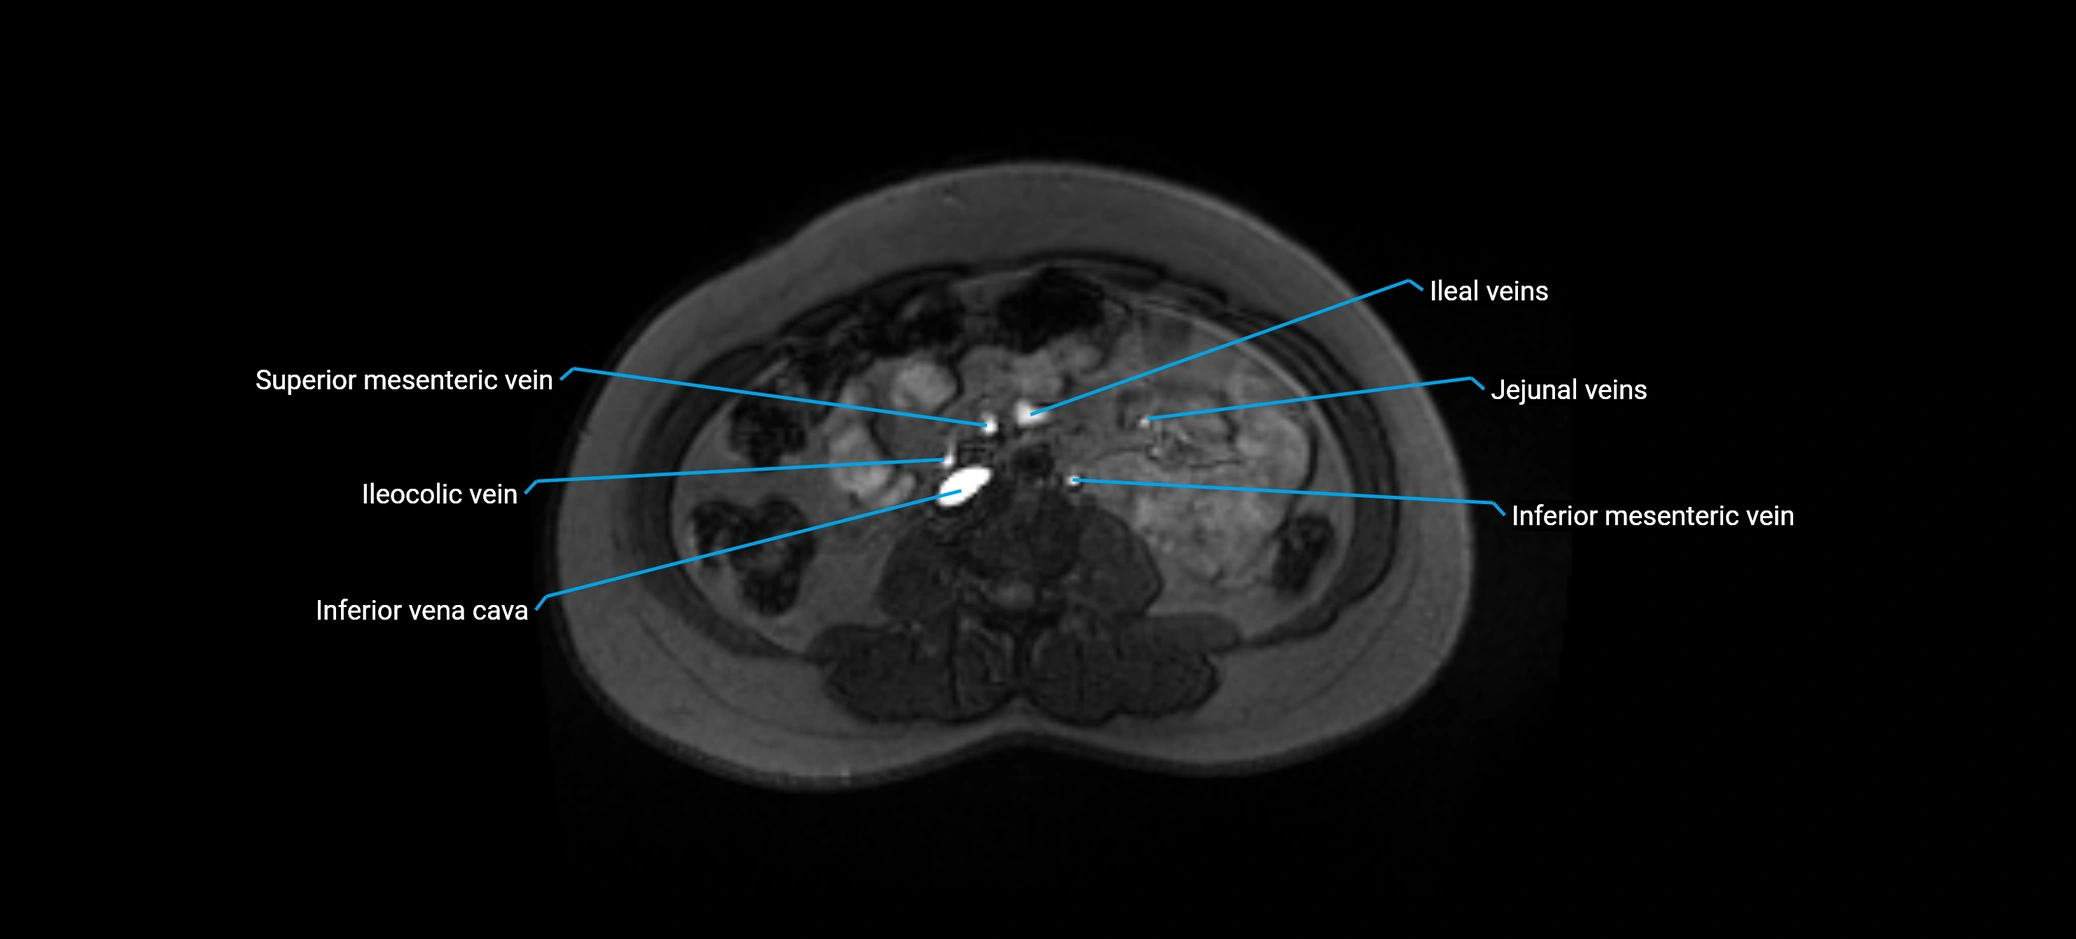

MRI image

image